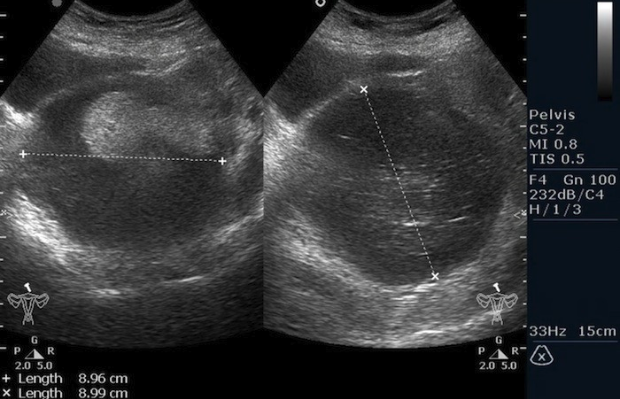

а)

Risunok3a.png

б)

Risunok3b.pngРисунок 3. – тератома яичника а –УЗИ, б - МРТ.